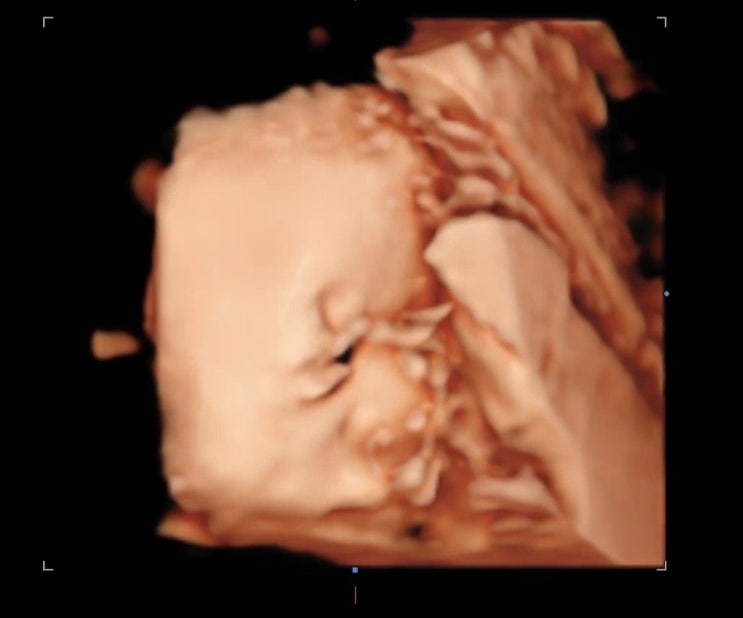

둘째임신) 32주차 5일 임신후기 증상. 태아 몸무게

32주 병원 방문. 아이는 잘 크고 있고 2주만에 500g이 늘었다. 저번달에는 한달만에 500g늘었는데 이번엔 2...